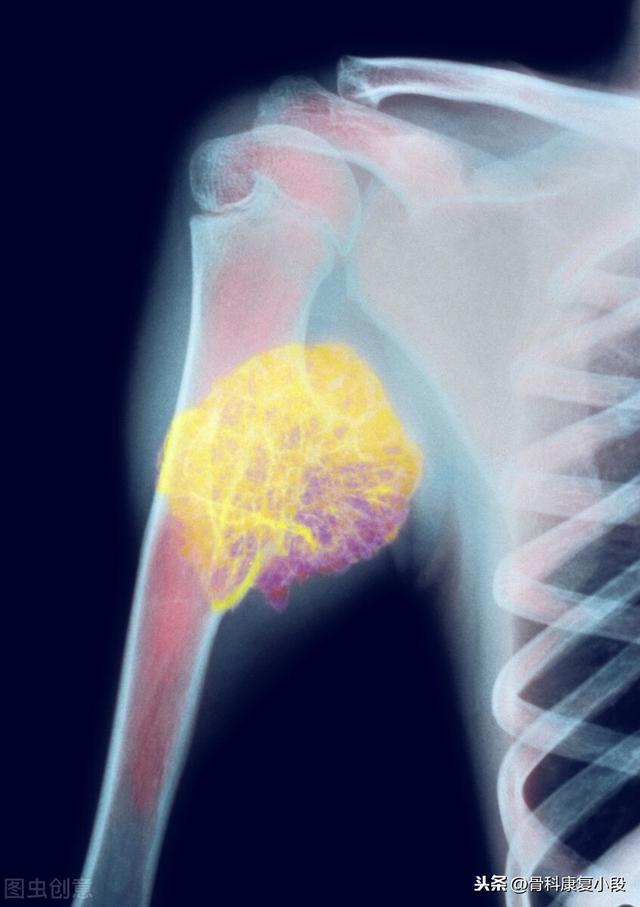

Métastase claviculaire d'un carcinome peu différencié ayant survécu à la tumeur pendant 5 ans.

Il s'agit d'un homosexuel de 58 ans qui a commencé à ressentir une douleur persistante lorsque son épaule a été légèrement étirée, et les radiographies ont révélé des foyers hypodenses :

Il s'agissait d'une fracture pathologique causée par des forces externes mineures sur la base d'une métastase osseuse. Une ponction a été effectuée et la pathologie était une métastase osseuse d'un adénocarcinome pulmonaire peu différencié.

Ce nodule irrégulier dans le poumon gauche est le foyer principal, qui ne mesure que 2,6 cm. Un cancer du poumon avec des métastases osseuses comme celui-ci n'est plus opérable. On ne peut rien y faire, le cancer du poumon est trop fréquent et certains des premiers symptômes sont atypiques, voire asymptomatiques.Dans environ 30 % des cancers du poumon, les symptômes des métastases sont la première manifestation, et les métastases sont détectées en premier avant que d'autres cancers du poumon ne soient détectés.

Heureusement, ce patient a été sensible au traitement et a été traité pendant 5 ans avec une combinaison de chimiothérapie et de traitements basés sur la thérapie ciblée.

Il s'agit de l'opération de fixation interne qu'il avait réalisée à l'époque pour une fracture de la clavicule, une fracture pathologique qui a beaucoup de mal à guérir seule sans intervention chirurgicale.

Son examen tomodensitométrique le plus récent a montré que la photo primaire avait beaucoup rétréci et il a eu la chance de survivre avec une rétention pendant plus de 5 ans !